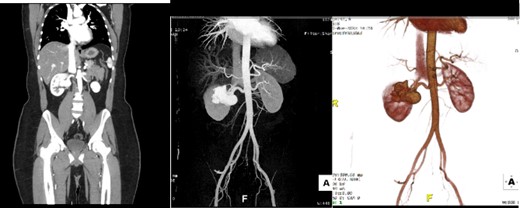

A 32-year-old male with no known chronic illnesses had a history of a motor vehicle accident five years ago, resulting in multiple bilateral rib fractures. An abdominal and pelvic CT scan conducted at the time did not reveal any other findings. The patient was admitted under the care of thoracic surgery for observation and pain management. After four years from the accident, the patient experienced intermittent right flank pain and made multiple visits to the emergency room. A CT scan of the kidneys, ureters, and bladder (CT KUB) was performed to rule out urolithiasis. The CT KUB showed multiple prominent structures with communication between the arterial and venous systems at the right renal hilum, suggestive of an intrarenal AVM with no apparent complications (Fig. 1). A CT run-off study confirmed the presence of an intrarenal AVM in the upper pole, measuring 2.9 cm (Fig. 2). The patient underwent angioembolization; however, multiple attempts at coil embolization failed due to the high risk of distal embolization. Subsequently, the patient underwent exploratory laparotomy for right AVF ligation. During the procedure, three AVF tracts were identified and ligated using clips. Prior to ligation, a thrill was palpable, but it was absent after the ligation. On the second postoperative day, a Doppler renal US was performed, which revealed patent right intrarenal arteries with normal resistive indices and normal peak systolic velocity in the right main renal arteries.

Run-off computed tomography angiography (CTA) showed right kidney hilum tortuous vascular arteriovenous communication of the arterial and venous system represents intrarenal AVM towards the upper pole measuring 2.9 cm.